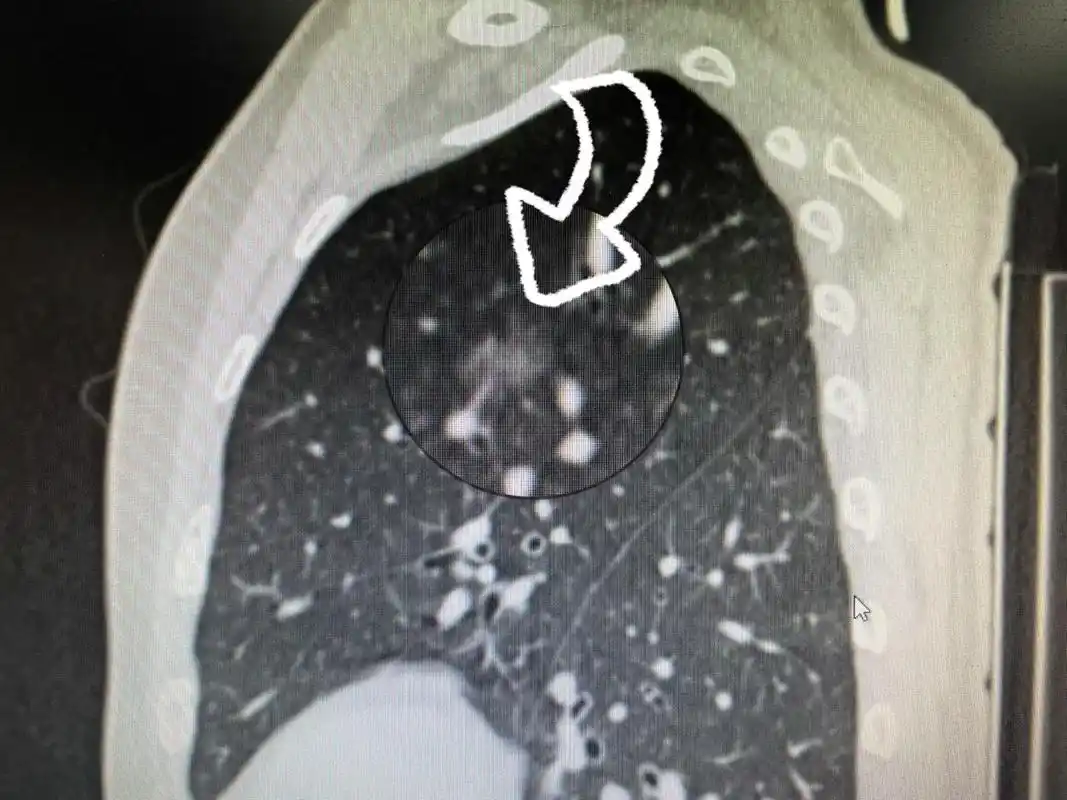

肺癌的诊断与治疗真不能千篇一律,也 - 抖音